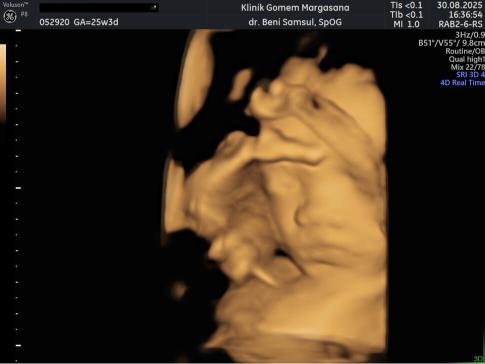

Perkembangan Janin 25 Minggu:

Pada minggu ke-25, berat janin semakin bertambah dan tubuh semakin besar. Tulang semakin kuat, dan gerakan semakin terasa jelas. Janin sering bergerak saat ibu sedang berbaring atau setelah makan. Perut ibu semakin terlihat besar dan kadang terasa gatal karena kulit meregang. Menggunakan pelembap bisa membantu mengurangi rasa tidak nyaman.

Gambaran Hasil USG Janin 25 Minggu